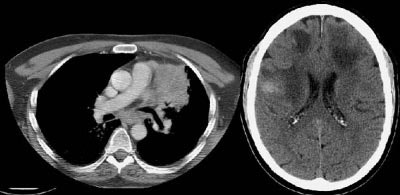

Example of brain metastases: This patient with non-small-cell lung cancer presented with left vocal cord paralysis. He did not have any neurological complaints. A central mass in the left lung was obstructing the left upper lobe bronchus (left image -- also note N2 subcarinal adenopathy). A head CT was requested by the patient's health care provider as part of the evaluation for his vocal cord paralysis and demonstrated multiple brain metastases, one of which is likely hemorrhagic (right fronto-parietal cortex).

NOTE: Click image to enlarge